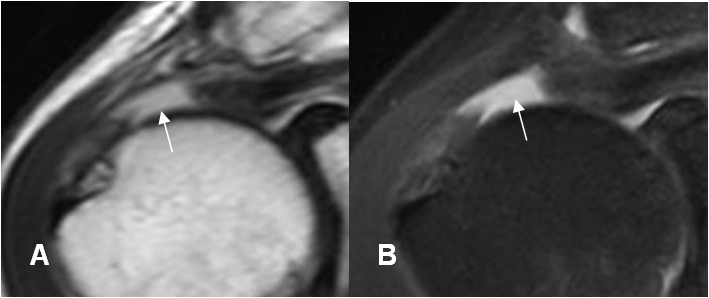

Fig 99. Ruptura del supraespinoso.

A: RM sagital en T2. No visualización del supraespinoso por debajo de la articulación acromioclavicular, secundario a ruptura,

B: RM sagital en T2. Ruptura del supraespinoso, en asocio a un acromión tipo 3.